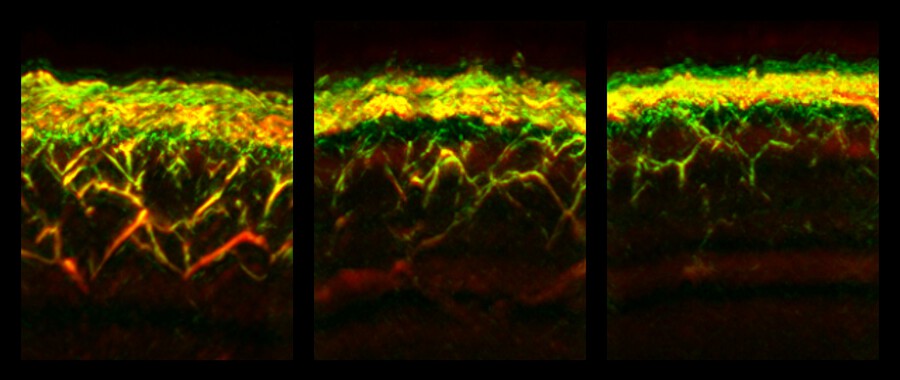

Bei einer einzelnen RSOM-Messung können gleichzeitig Daten zu verschiedenen Tiefen der Haut gewonnen werden. Dadurch konnten die Forschenden erstmals feststellen, dass sich Diabetes unterschiedlich auf Gefäße in verschiedenen Hautschichten auswirkt: Während beispielsweise die Zahl der Gefäße und Verästelungen in der sogenannten dermalen Ebene bei Diabetiker:innen verringert waren, waren sie dichter unter der Hautoberfläche, in der sogenannten epidermalen Ebene, erhöht.